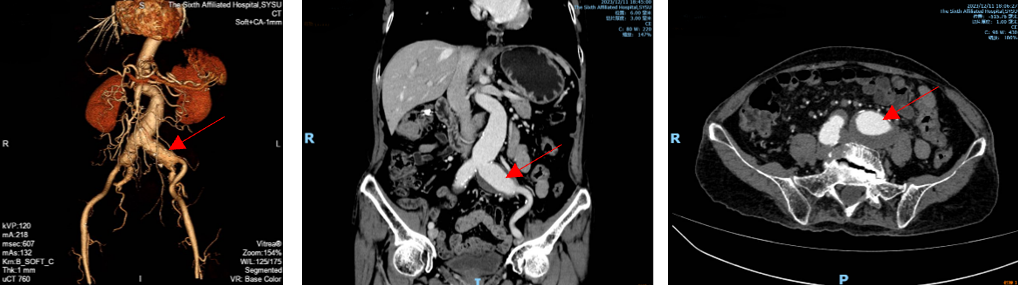

术前CTA重建提示:腹主动脉远段、双侧髂总动脉、左侧髂内动脉管腔扩张,左侧髂总动脉瘤最大直径超过42mm。

根据黄叔的影像资料,张波团队发现他双侧髂总动脉瘤瘤体较大,累及双侧髂内、髂外动脉的分叉口。在覆膜支架隔绝时,为获取足够的锚定,就需要栓塞及封堵双侧髂内动脉。

考虑黄叔肠癌合并腹主动脉及髂动脉瘤,病情复杂,张波团队认为应行腹主动脉瘤及双侧髂动脉瘤支架隔绝术,同时,为避免双侧髂内动脉栓塞导致的相关并发症,可采用目前较为先进的IBD技术(髂动脉分支覆膜支架植入),在髂内动脉瘤临近上的分支处也进行覆膜支架植入,为黄叔保留正常的右侧髂内动脉。

术中行右侧髂内动脉IBD及腹主动脉-双侧髂动脉瘤支架隔绝

术后半年复查CT显示腹主动脉-双侧髂动脉瘤完全隔绝,右侧髂内动脉血流通畅。